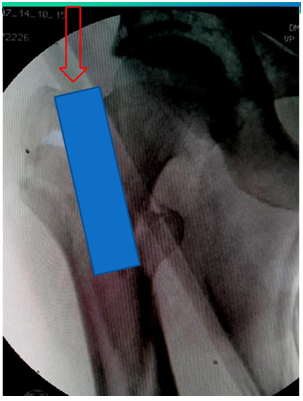

Failure of closed reduction

1. If there is failure of closed reduction better to open the fracture and achieve reduction by bone spikes/reduction clamp/ circlage wire etc.

2. Nail will not ensure reduction.

3. If reduction is not there the head screws will go into malposition (Figure 7).

Figure 7 Failure of closed reduction.